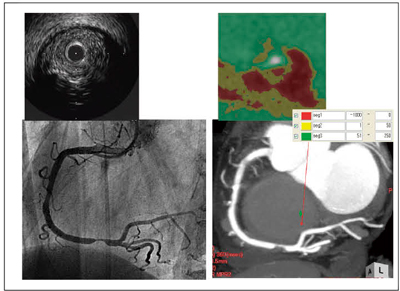

(2) の動脈硬化病変性状を観察する場合には血管短軸にSlab方向を合わせ,厚みは最薄厚にして評価します。われわれが通常評価しているポイントは,PCI治療でのトラブルにつながる「末梢塞栓に関連するlipid coreの可能性のあるプラーク」と「治療困難や拡張不良につながる可能性のある石灰化」の存在です。前者はCT値をカラーマップ(上記zioTerm2009などで可能)で“−1000〜0”を赤,“1〜50”を黄,“51〜250”を緑に色分けした際の“血管内に存在する黄で囲まれた赤”をチェックし,後者はウインドウ幅とレベルを調整,もしくはカラーマップで“600〜2000”をピンクに色分けし,画像調整後の石灰化像またはカラーマップでピンクが血管全体を占めるものをチェックしています。これらのチェックポイントに合致する病変では,PCI治療のトラブルが高くなるため,配慮が必要になります。

図6に,緊急症例の心臓CTをSlab MIPで評価したことによって,素早く左主幹部病変であることを診断,冠動脈造影で確認し引き続きPCI治療を行うことができた症例を示します。この症例では,心電図は左室肥大所見があるものの,緊急的な心筋虚血があるとは思われず,血液検査でも白血球数・HFABPを含め異常値を認めず,心エコーでも異常が指摘できませんでした。もしSlab MIPが使えなければ夜中の緊急心臓CTも行えず,この左主幹部の高度狭窄病変に気付かないままであった可能性は非常に高いと思われます。改めて,Slab MIPの重要性を再確認した一例でした。

図6 緊急症例に対するSlab MIP像を用いた心臓CT評価法の有用性 心電図・血液検査・心エコーで急性冠症候群を疑わせる所見を認めなかったが,心臓CTが左主幹部病変を指摘できた症例。

心電図・血液検査・心エコーで急性冠症候群を疑わせる所見を認めなかったが,心臓CTが左主幹部病変を指摘できた症例。